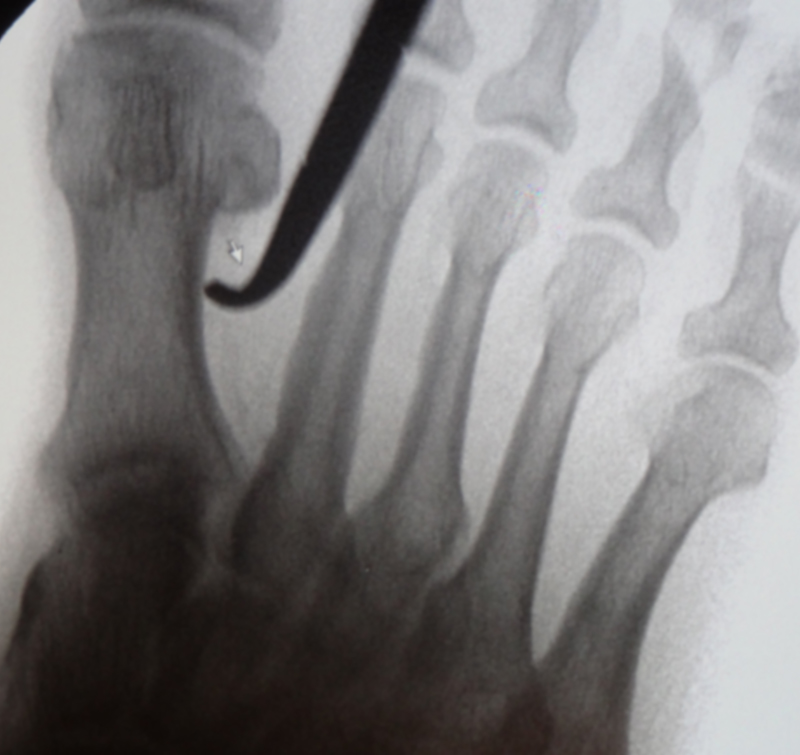

Ein häufig angewandtes Verfahren zur Korrektur eines erhöhten intermetatarsalen Winkels ist die laterale basale Closing Wedge Osteotomie des Os metatarsale I, entweder als Einzelverfahren oder in Kombination mit einer Isham-Osteotomie (sogenannte Doppelostetomie des 1. Mittelfußknochens) 2.

Die minimalinvasive Basisosteotomie des 1. Strahles stellt – entsprechend offenen Verfahren - die Operationstechnik mit dem größten Korrekturpotential dar. Sie kann entweder mit einer medialen Exostosenabtragung des Metatarsale-I-Köpfchens oder aber mit einer zusätzlichen minimalinvasiven subcapitalen medialen Closing wedge Osteotomie (Isham) kombiniert werden 2.  Diese Doppelosteotomie stellt ein hochpotentes Werkzeug zur Korrektur von schweren Hallux Valgus Fehlstellung dar. Im Unterschied zu offenen Verfahren an der Basis des Os metatarsale I sind minimal invasiv immer nur in Closing Wedge Technik möglich, womit eine leichte Verkürzung des 1. Strahls verbunden ist. Die Indikation entspricht dem offenen Techniken.

• Bei hohem Hallux valgus Winkel oder pathologischem Gelenkflächenwinkel besteht die Indikation zu einer zusätzlichen Isham Osteotomie 2, die im Wesentlichen der offenen Reverden Green Osteotomie entsprecht.